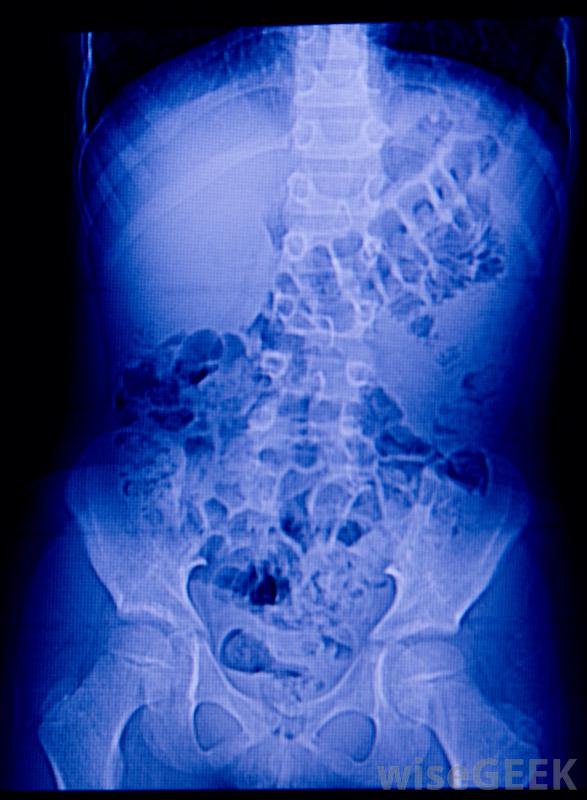

腹部X光检查应该能够检测到腹腔内的剖腹手术海绵。

一些制造商使用无线电不透明带或丝线。在关闭手术部位之前,可以对患者进行x光检查,以确保发现并处理掉任何掉队的人。当患者出现海绵滞留症状,如剧烈腹痛和压痛时,这些特征也很有用;x光片可以快速确定是否存在剖腹手术海绵或是其他原因引起了问题。